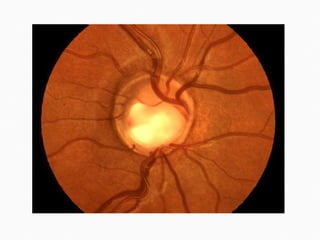

Endophthalmitis   is a serious infection of the intraocular tissues, usually following intraocular surgery, or penetrating trauma.  Glaucoma  may occur and it may be very difficult to control. It is usually associated with inflammation, specially when little fragments or chunks of the nucleus get access to the vitreous cavity.  Patients may experience  Spontaneous bleeding  from the wound and  Recurrent inflammation  after surgery. Flashing, floaters, and double vision may also occur a few weeks after surgery.

It is a inflammation of inner coat of eye ………….. It may occur following the intraocular surgery  such as cataract or glaucoma filtration surgery etc./…..